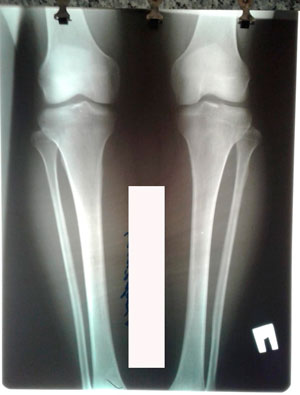

Исходник - 37 лет.

Дата операции - 04.08.2020